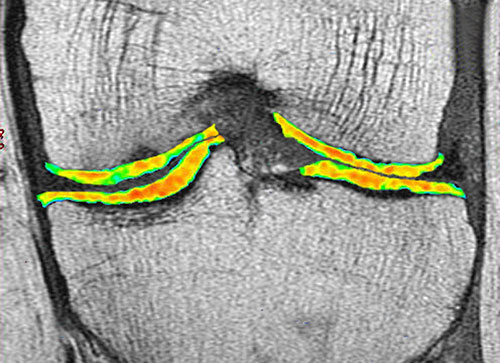

Advanced Imaging Techniques